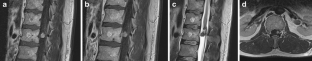

Fig. 4